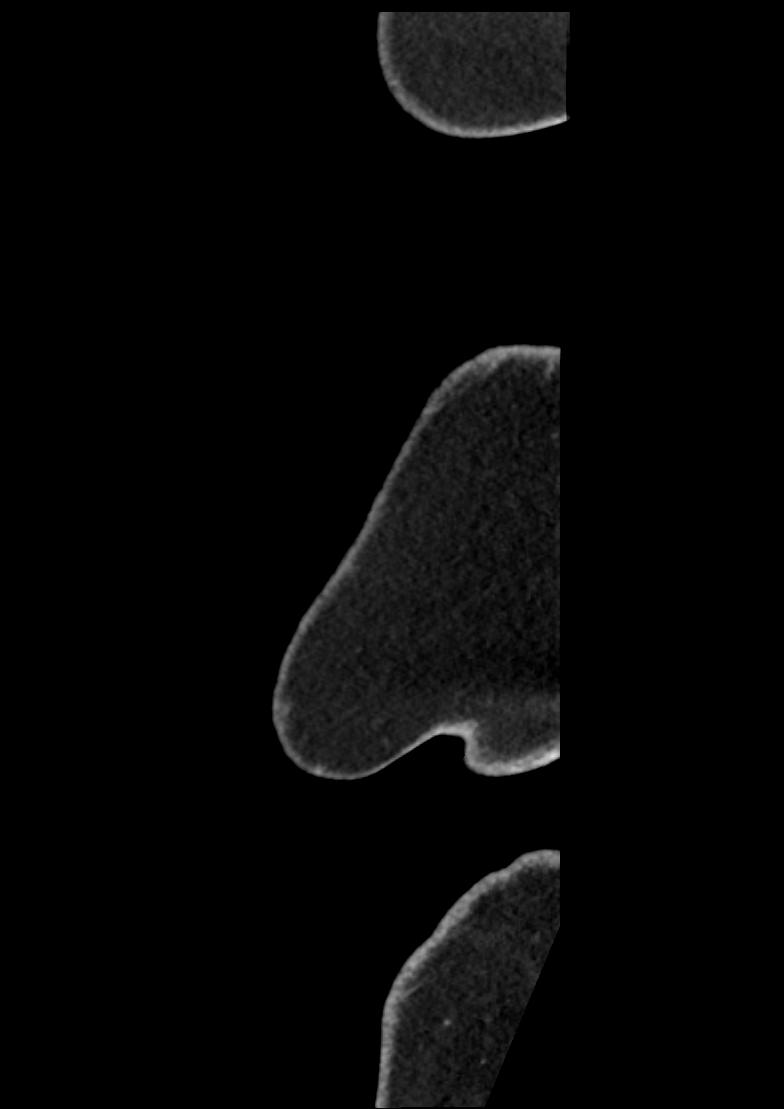

Patient: Padmakumar A. , *1988-04-24, PID: 3000069741773230809

Study Description: CT ABDOMEN

Image Series: Abdomen Sag 3mm [4]

<< Previous | Image 156 of 158 | Next >>